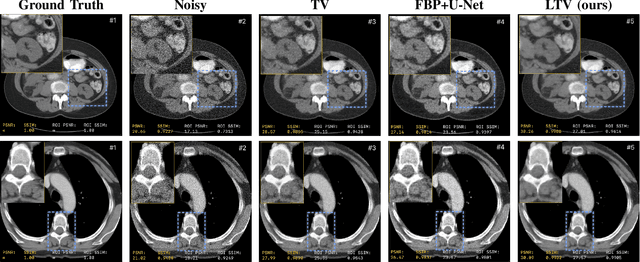

Abstract:Although Total Variation (TV) performs well in noise reduction and edge preservation on images, its dependence on the lambda parameter limits its efficiency and makes it difficult to use effectively. In this study, we present a Learnable Total Variation (LTV) framework that couples an unrolled TV solver with a data-driven Lambda Mapping Network (LambdaNet) predicting a per-pixel regularization map. The pipeline is trained end-to-end so that reconstruction and regularization are optimized jointly, yielding spatially adaptive smoothing: strong in homogeneous regions, relaxed near anatomical boundaries. Experiments on the DeepLesion dataset, using a realistic noise model adapted from the LoDoPaB-CT methodology, show consistent gains over classical TV and FBP+U-Net: +2.9 dB PSNR and +6% SSIM on average. LTV provides an interpretable alternative to black-box CNNs and a basis for 3D and data-consistency-driven reconstruction.